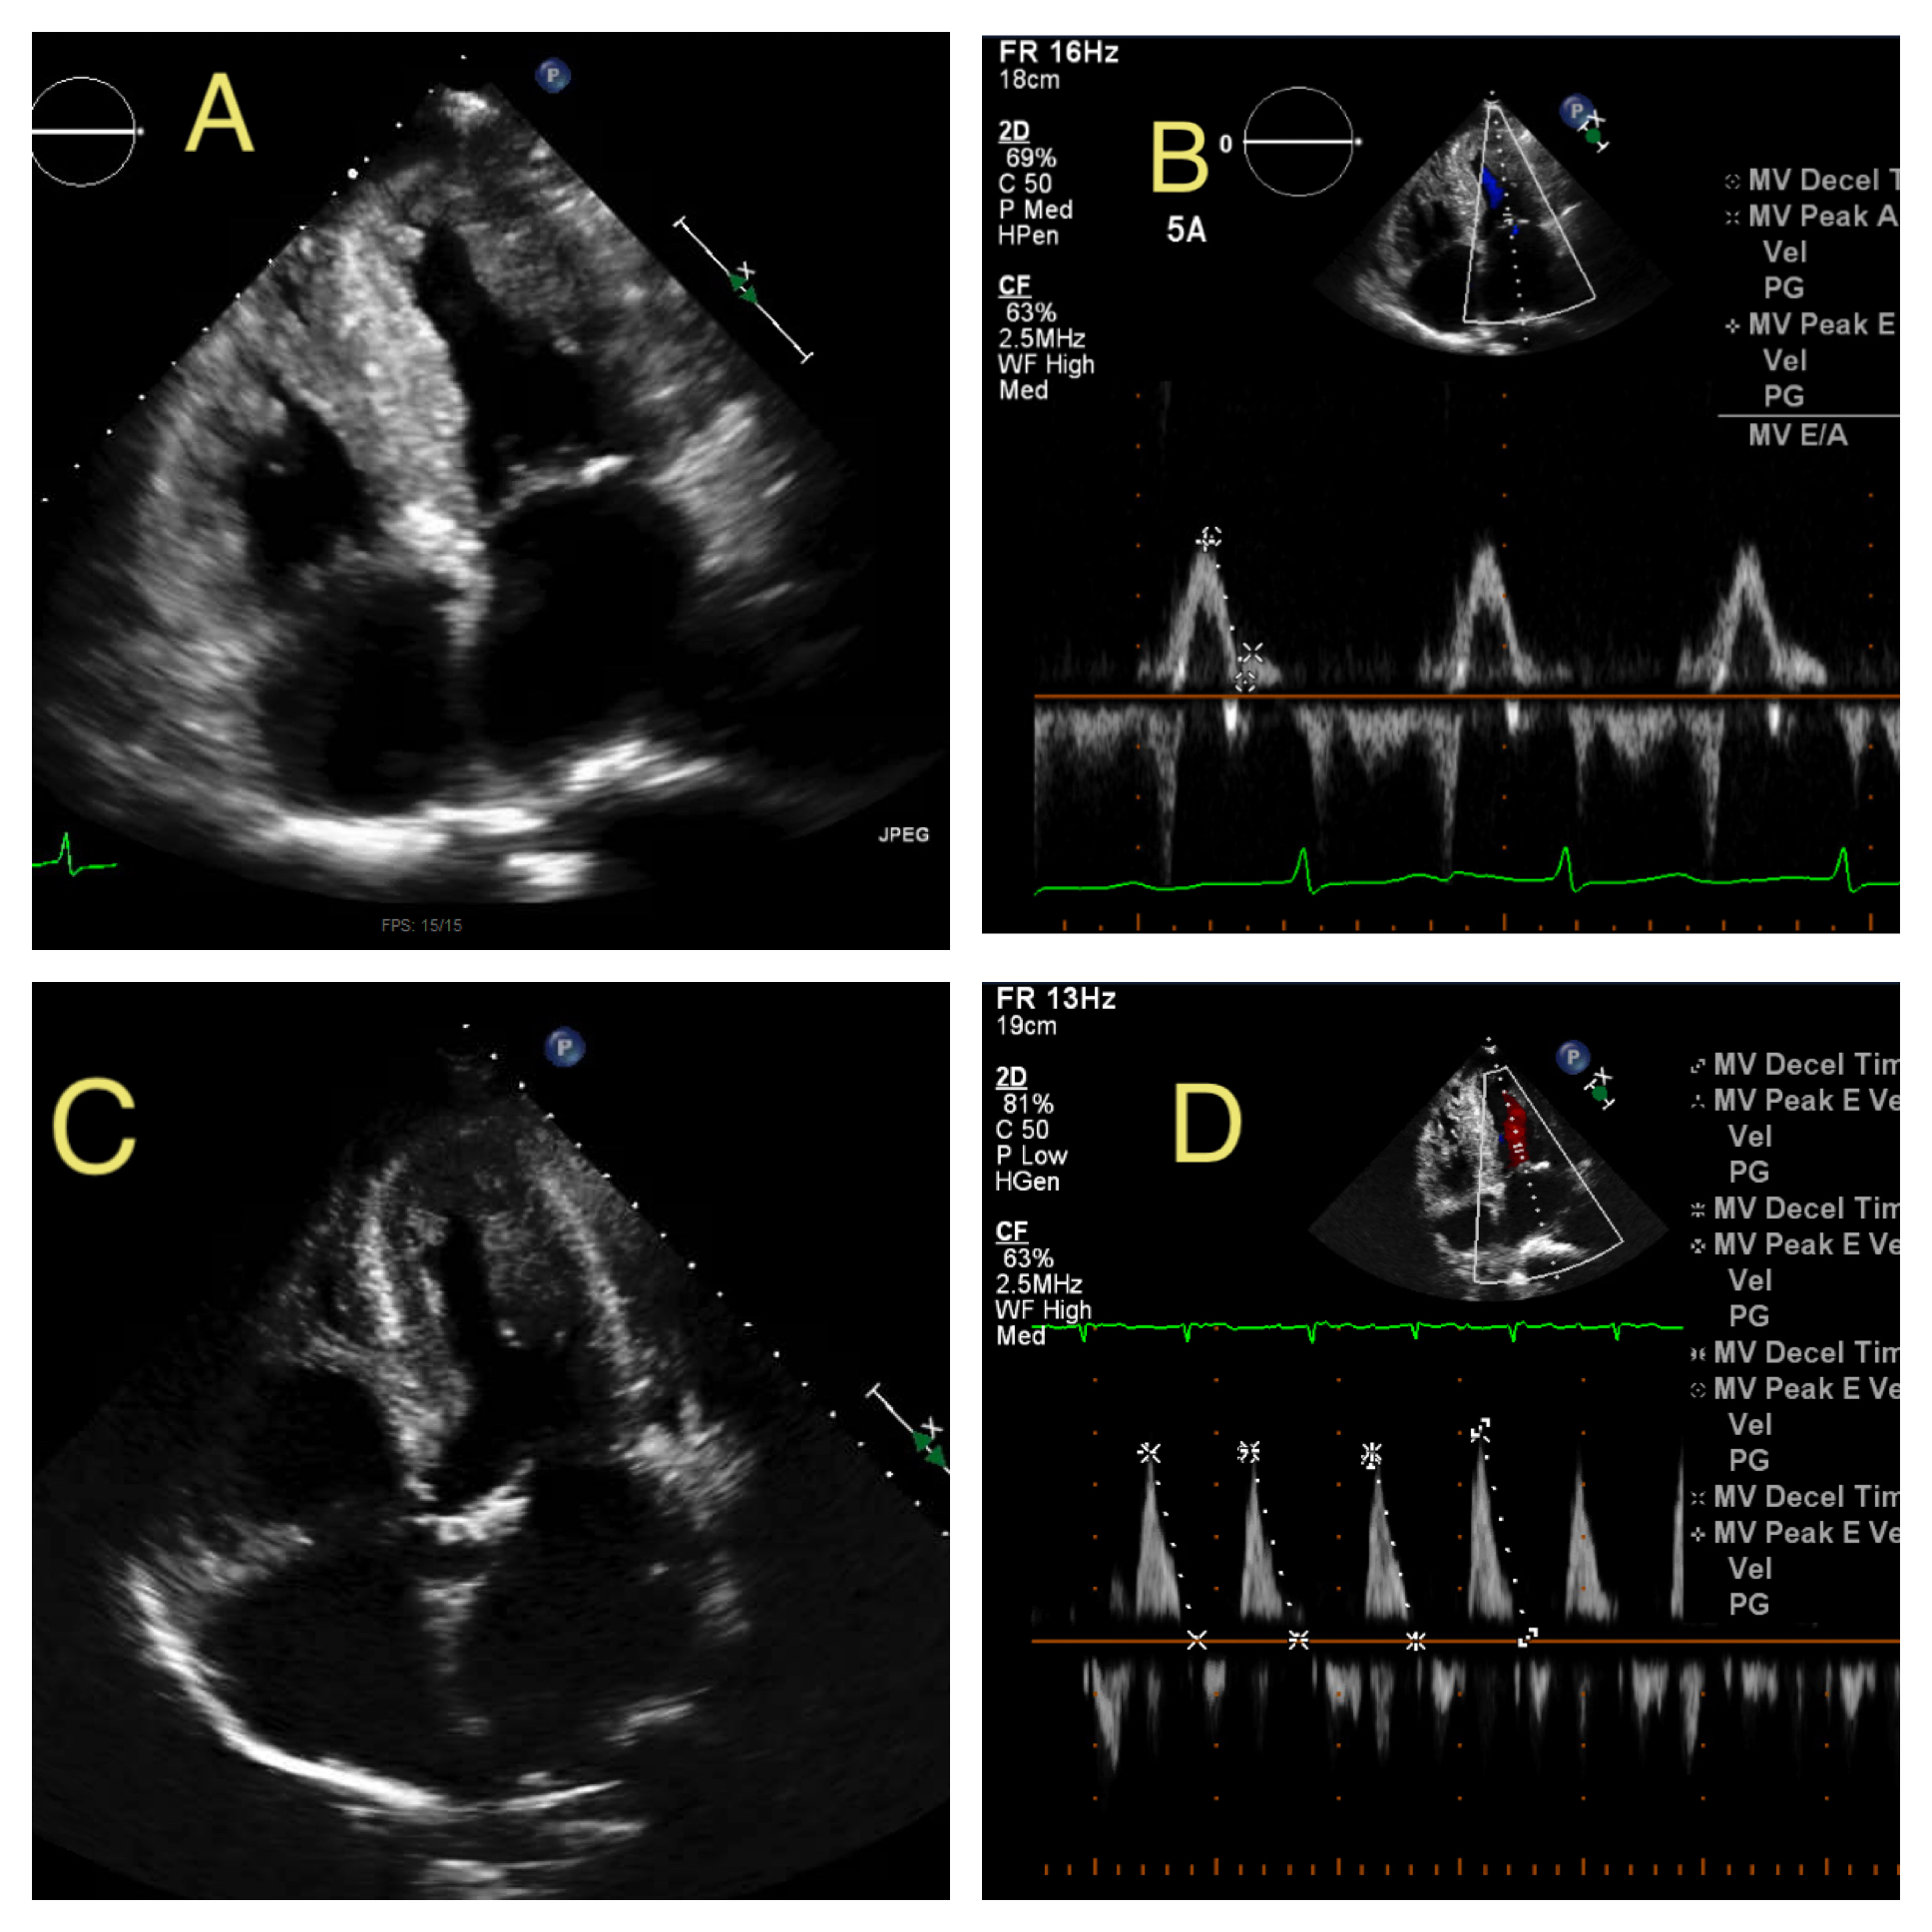

Transthoracic echocardiography (ECHO) was obtained which revealed a progressive decline in left ventricular ejection fraction (LVEF) to 25-35% along with worsening diastolic dysfunction with E/A 3.5 and medial E/E’ 24 despite patient’s adherence to medical management. ECHO at HF diagnosis (3-years prior) showed LVEF 50-55% and mild diastolic dysfunction E/A 0.78. Repeat ECHO 1.5 years prior revealed a decline in LVEF to 30-40%. Cardiac MRI was performed to rule out apical ventricular thrombi and showed diffuse late gadolinium enhancement concerning for amyloidosis. Follow up nuclear bone imaging revealed increased cardiac uptake greater than bone, suggestive of grade III cardiac amyloidosis. Fat pad biopsy and mass spectrometry confirmed tissue transthyretin amyloidosis. The patient was managed conservatively with diuretics and discharged with appropriate follow ups in place. His home lisinopril and metoprolol were discontinued due to concerns that they may worsen amyloidosis symptoms.